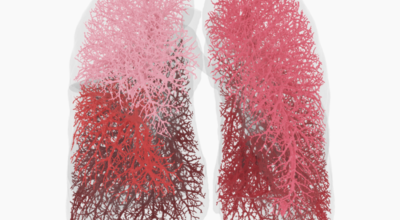

폐란?

척추동물 중 공기호흡을 하는 동물의 호흡기관으로, 허파 또는 폐장이라고도 하며, 구조적으로 기관지와 혈관이 모여 이루어져 있습니다. 폐는 산소와 이산화탄소(탄산가스)를 교환하는 가장 중요한 기관입니다. 사람에게는 좌우 한 쌍이 있으며, 전체적으로 반원뿔 모양을 하고 있습니다. 흉강 중앙에 있는 종격을 사이에 두고 가슴의 좌우에 자리 잡고 있는데, 좌측에 심장이 있어 오른쪽 폐가 조금 더 큽니다.